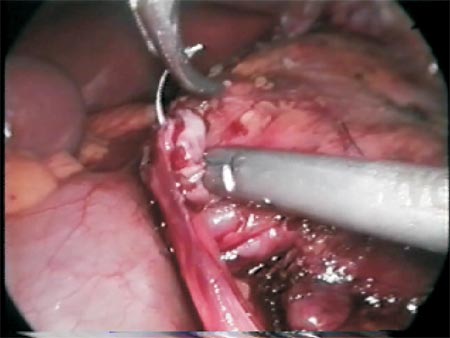

After the section of the stenosed area, the ureter spatulation (Photo 5) and the completion of the posterior wall anastomosis (Photo 6), the Levine catheter is disconnected from the ureteral catheter and a retrograde hydrophilic guidewire is inserted through the external orifice of the ureteral catheter which will be exposed by the left hand trocar (Photo 7 and Figure 5) with care in order to avoid the anastomosis posterior stitches to tear (during this manipulation if possible an atraumatic forceps should be maintained).

Photo 5 - Spatulation of the ureter.

Photo 6 - Constructing the posterior wall of the anastomosis.

Photo 7 - Retrograde passage of the guidewire guided by an atraumatic forceps outside the left hand port.